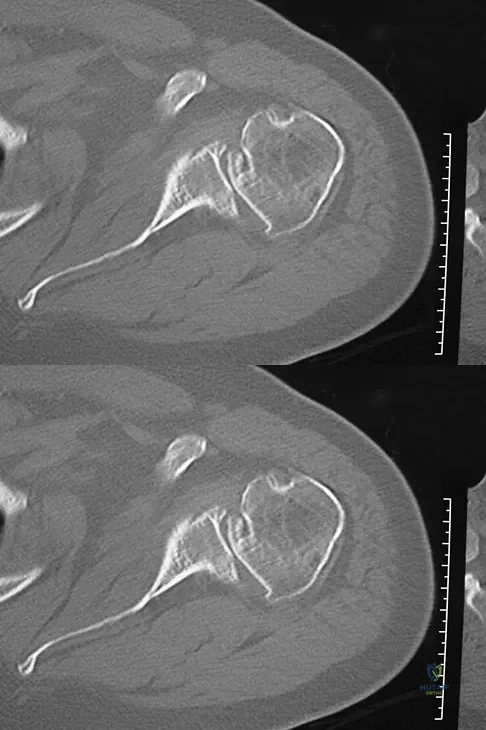

A 68-year-old man had a 3-year history of shoulder pain that failed to respond to nonsurgical management. Examination reveals forward elevation to 120 degrees and external rotation to 30 degrees. True AP and axillary radiographs and an axial CT scan are shown in Figures 1a through 1c. What management option would lead to the best long-term results?

A 30-year-old right hand-dominant woman is seen in the trauma unit after a high-speed motor vehicle accident. She sustained a right shoulder anterior dislocation that is gently reduced under sedation. A CT scan is shown in Figure 3. If left untreated, the patient is at greatest risk for